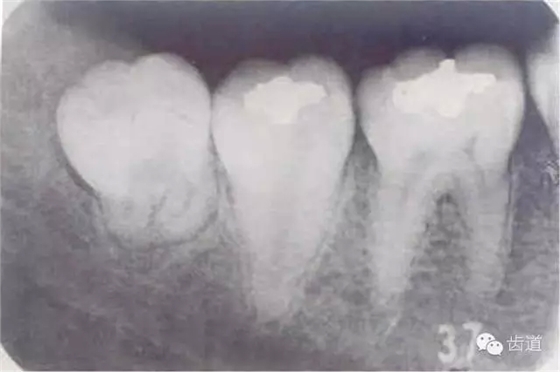

四、智齒冠周炎

一)定義

下頜第三磨牙在萌出過程中,由于萌出不全或阻生,牙冠周圍軟組織發(fā)生的炎癥。又稱智齒冠周炎。

二)病因

1.人類進化過程中,下頜骨體逐漸縮短,導致第三磨牙萌出空間不足,表現(xiàn)為部分萌出、牙位偏斜甚至完全埋伏阻生

2.冠周齦瓣形成盲袋,食物殘渣進入后不易清除,細菌在此生長繁殖

3.雙向受力,局部血運差,細菌入侵

4.全身抵抗力下降時,急性發(fā)作

三)臨床表現(xiàn)

1.局部癥狀:早期僅磨牙后區(qū)不適→炎癥加重時,局部有自發(fā)性跳痛,放射至耳顳區(qū)→波及咀嚼肌,出現(xiàn)不同程度的張口受限,咀嚼和吞咽時疼痛加重,口腔清潔差,口臭

2.全身癥狀:炎癥加重時,出現(xiàn)發(fā)熱、畏寒、頭痛等

四)檢查所見

1.智齒萌出不全

2.牙冠周圍軟組織紅腫、糜爛、觸痛

3.齦瓣處形成盲袋,內(nèi)有膿性分泌物,有時形成冠周膿腫

4.嚴重時可見咽側壁及舌腭弓紅腫,患側頜下淋巴結腫大、壓痛。

6.webp.jpg

7.webp.jpg

8.webp.jpg

9.webp.jpg